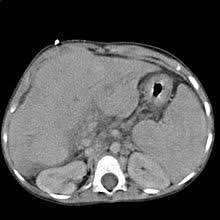

Dekompensierte Leberzirrhose Child C

Fibrose und Zirrhose der Leber.